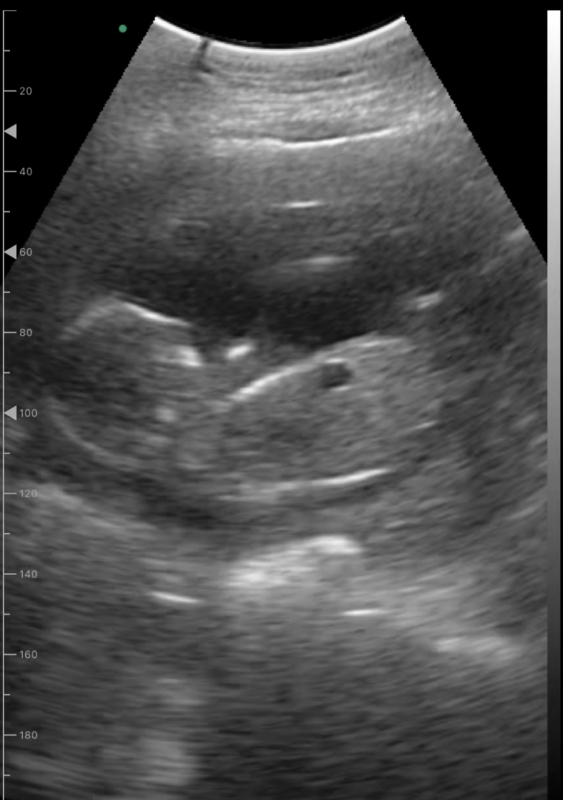

現在妊娠17週。自宅で家庭用エコーを使って毎日胎児を確認しています。

心臓が動いていることにホッとしていますが、時折写真のような黒くて丸い影が映ることがあります。今までの健診では特に指摘を受けたことはありません。次回の健診が一ヶ月後のため心配で、、。これは何か分かりますでしょうか?

実際に拝見していませんので、はっきりとしたことは明言できませんが、もしかすると、胃や腸に見られる空気なのかもしれませんね。特に健診で何も指摘されていないのでしたら、ご心配なものではないと思いますよ。また気になるようでしたら、健診の際にでもご確認なさってくださいね。